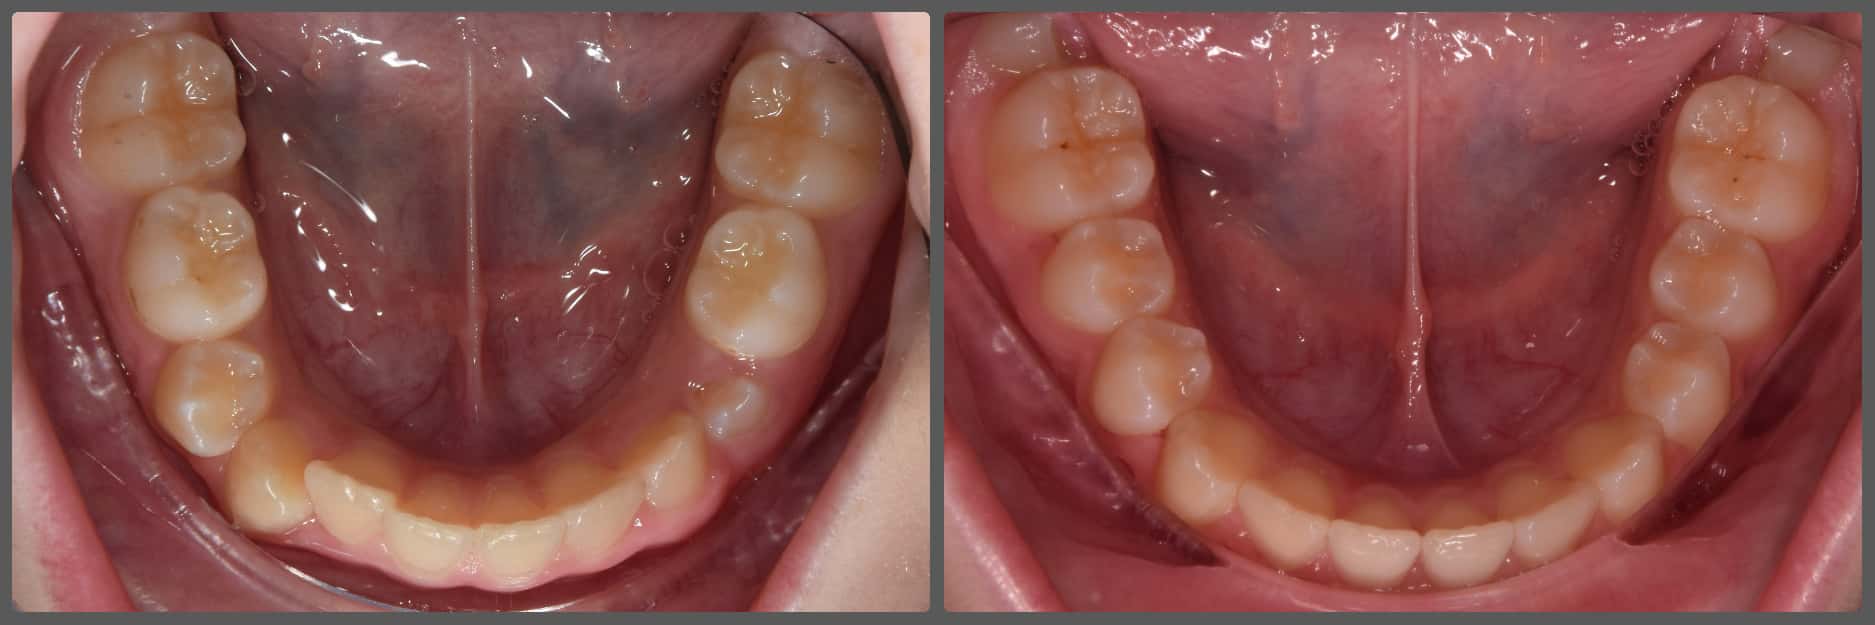

Balázs súlyos alsó torlódása miatt keresett fel magánrendelésemen. A diagnosztikus vizsgálatok során előbbin túl alsó-felső fogívszűkületet, valamint nyitott harapási hajlamot állapítottam meg. Kezelését Pitts21 alsó-felső rögzített fogszabályozó készülékkel kezdtük meg. A nyitott harapási hajlamot a hátsó fogakra helyezett harapásemelővel kontrolláltuk. A torlódott fogaknak tolórugóval és interproximális redukcióval teremtettünk helyet, és intermaxilláris gumihúzással tökéletesítettük a harapást. A fogszabályzó kezelés teljes időtartama alatt Balázs 110%-osan együttműködő volt, ezért 21 hónap alatt sikerült kiemelkedő végeredményt elérnünk.